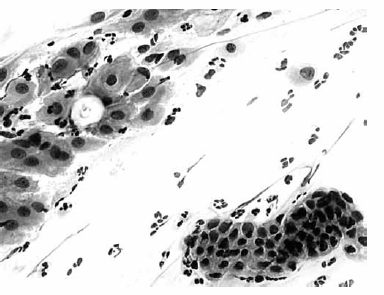

Nas questões de números 46 a 60, assinale a alternativa que melhor corresponde ao diagnóstico do quadro microscópico apresentado.